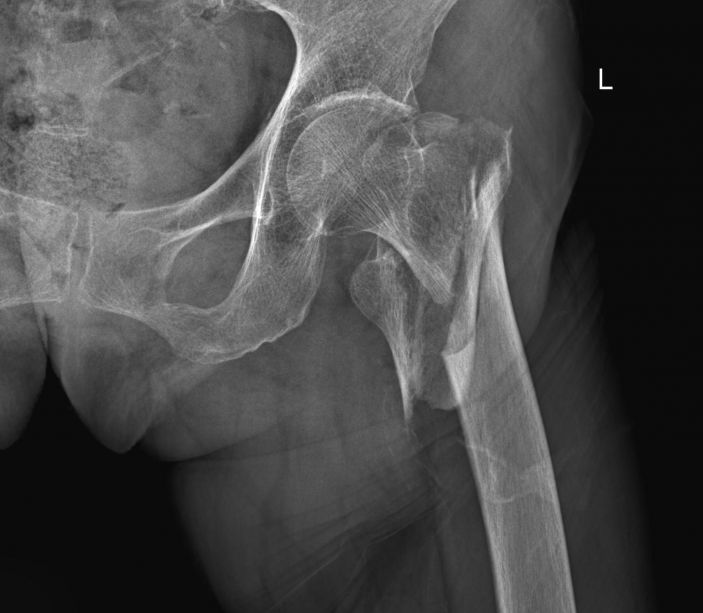

據了解,林老太于4月18日在家不慎跌倒,左臀着地,緻左髋關節活動受限,左下肢外旋90度畸形,無法站立。家人随即将老太送往我院,收住外四科。經CT+三維重建顯示爲左側股骨粗隆間、股骨上段粉碎性骨折。由于老太已到期頤之年,骨折較嚴重,其家屬異常擔心。

△術前